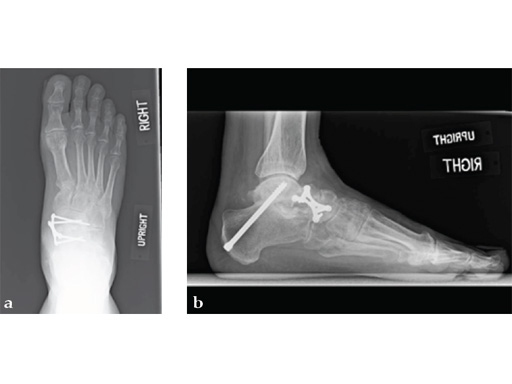

Case 4: First TMT fusion plate

A 60-year-old woman with pes plano abductovalgus (flatfoot deformity).

Case provided by Andrew Sands, New York, New York, USA

The patient was treated by headless compression screw 6.5 tuber osteotomy, TMT plantarflexing osteotomy, and first TMT fusion a plate.